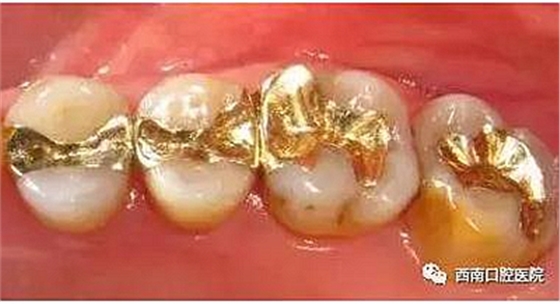

我們來看下各個材料充填之后的顏值吧!

黃金的耐磨性很高,對齲洞邊緣有很優(yōu)秀的適應性并且完全無毒,是很好的充填材料,但是黃金價格昂貴且對牙醫(yī)技術要求高。